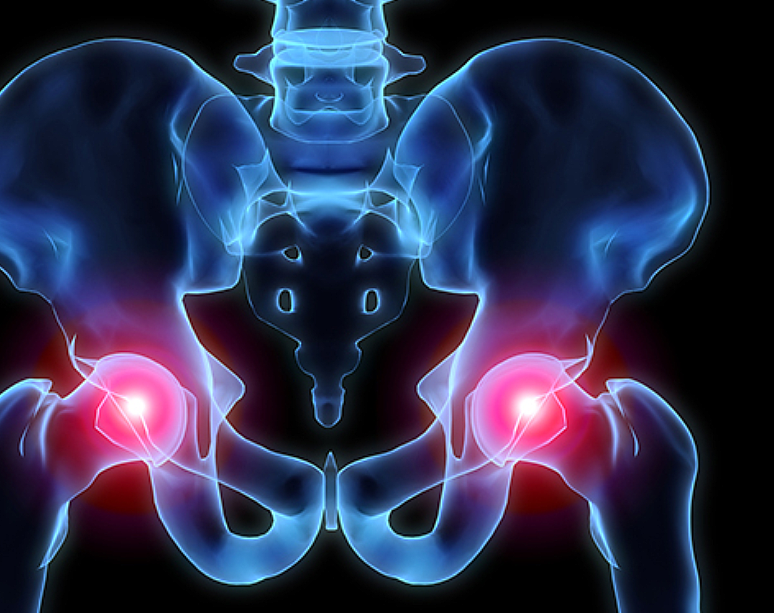

고관절 통증 증상(엉덩관절)은 오른쪽과 왼쪽의 골반과 넙다리뼈가 연결된 관절의 통증을 얘기합니다.고관절은 상체의 하중을 분산시키는 역할을 하며, 걷는 동안 체중의 3배, 달리는 경우 10배에 가까운 하중을 받습니다. 다른 관절과 마찬가지로 감당하기 어려운 충격이나 무게가 가해지면 고관절 통증 증상이 발생합니다. 퇴행성 고관절염, 대퇴골 골절, 대퇴골두 무혈성 괴사, 선천성 고관절 탈구 등이 대표적인 고관절 통증 질환입니다.

고관절은 골반 뼈 속에 공처럼 생긴 대퇴골의 골두가 맞물린 관절입니다. 대퇴골두는 다른 부위에 비해 혈액 순환 장애가 쉽게 올 수 있으며, 혈액 순환 장애는 대퇴골두 무혈성 괴사를 유발합니다. 뼈가 썩으면 몸의 하중을 정상적으로 견디지 못해 미세구조에 골절이 생기고, 심각한 통증이 발생합니다.

뚜렷한 원인은 밝혀지지 않았지만, 과다한 음주가 골 괴사의 위험을 높이는 가장 큰 원인입니다. 형외과 전문의는 “대퇴골두 무혈성 괴사는 여성보다는 남성에게서 많이 나타나고 환자의 60%는 양쪽 고관절 통증 증상에 모두 나타난다”며 “발병 요인 중 한국 남성들의 음주 습관이 큰 원인으로 꼽히고 있습니다. 자주 술을 마시게 되면 혈액에 콜레스테롤과 지방 등이 쌓이게 되고 이것이 혈관을 수축시키는데, 이때 혈압이 증가하고 혈액이 응고되면서 혈액 순환을 방해하게 됩니다. 과음으로 인해 급성으로 진행돼 고관절 뼈가 주저 앉는 사례도 있어 조기에 치료받는 것이 중요합니다.